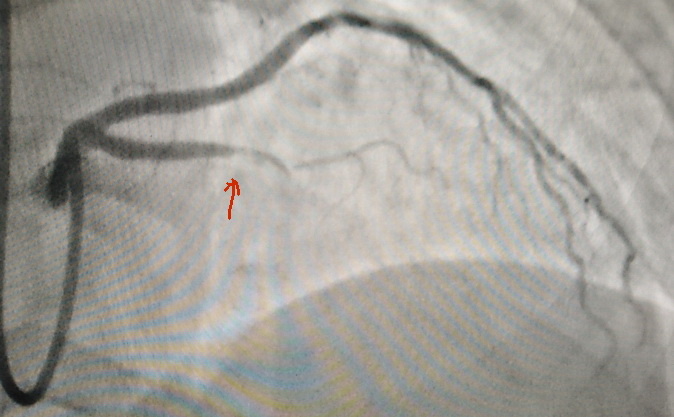

И вот что удалось сделать хирургам:

стрелка показывает на бляшку. В норме контрастное вещество должно заполнять артерию, но бляшка препятствует нормальному кровотоку.

На коронарографии выявлен стеноз передней межжелудочковой ветви.